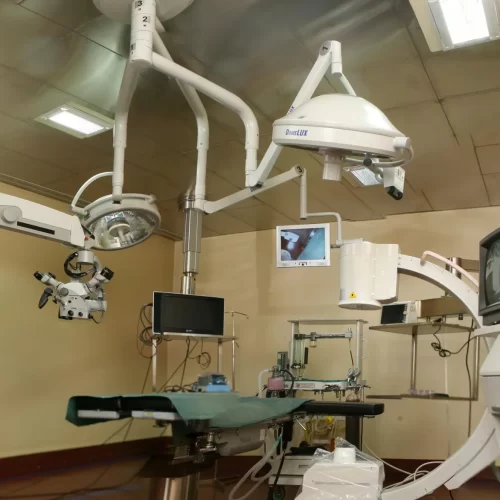

Today, technological advances in optics and the development of advanced camera and display systems such as 4K technology have made spine surgery a simpler and safer procedure. These are known as minimally invasive techniques because they require only small skin incisions. There are two main techniques: microdiscectomy and endoscopic discectomy. In a microdiscectomy, a small incision is made in the skin, and the surgery is performed with the help of an operating microscope that provides a magnified view of the affected area. An endoscope is a thin, specialized telescope that can be inserted into tissues through a small incision to reach the target area. A camera system and display monitor are connected to the scope to view the interior of the body, allowing the surgeon to operate while viewing an enlarged image of the deeper tissues.

Special instruments and equipment are required for this surgery. Using this technique, surgeons can not only remove the disc but also widen the spinal canal in cases of stenosis and relieve nerve root compression caused by other factors, all with the help of the endoscope. This procedure requires specialized training in the use of endoscopic equipment. KKOH has pioneered the use of endoscopic surgery in the treatment of spinal disorders. For further details or to book an appointment with a spine specialist, please contact the reception.

Our endoscopy system uses the advanced 4K technology from Rivo spine, Germany. This technology involves high end image capture system giving natural colours to the tissues.